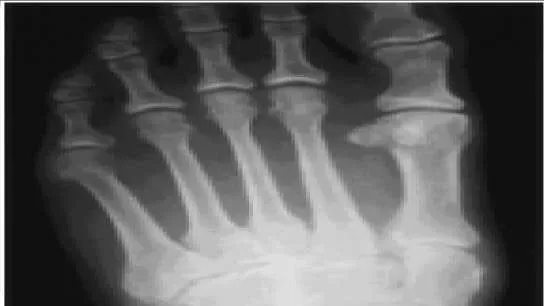

A 53-year-old man presents with a swollen foot. He does not recall any injury to the foot, and he has minimal pain. He does not have any pertinent medical history. The clinical and radiographic appearance of the foot is presented (Slide 1 and Slide 2). Based upon the information, the recommended treatment of this injury is:

Correct Answer: Open reduction and internal fixation (ORIF)

Patients with neuropathy may present for the first time with a neuropathic dislocation (C harcot neuroarthropathy) even before the cause of the neuropathy is diagnosed. The recommended treatment of an acute neuropathic midfoot dislocation is open reduction and primary arthrodesis. Although ORIF without arthrodesis may be considered, recurrent deformity frequently occurs.